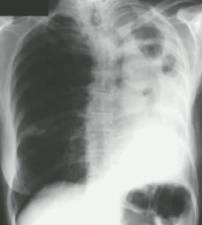

慢性空洞性肺曲霉病(CCPA):最常见,单发或多发的肺空洞(薄壁或厚壁),空洞内可包含一个或多个曲菌球或不规则的腔内物质,具有曲霉菌血清学和微生物学依据,并有明显肺部和全身症状,至少3个多月的观察有放射影像学进展(新发空洞,空洞外周浸润增加及纤维增生增加)。

慢性纤维化性肺曲霉病(CFPA):常因未经规范治疗的CCPA发展而来,至少有两个肺叶的严重纤维化破坏,伴肺功能丧失。而单发空洞伴一个肺叶的严重纤维化性破坏,简称为CCPA影响的肺叶。